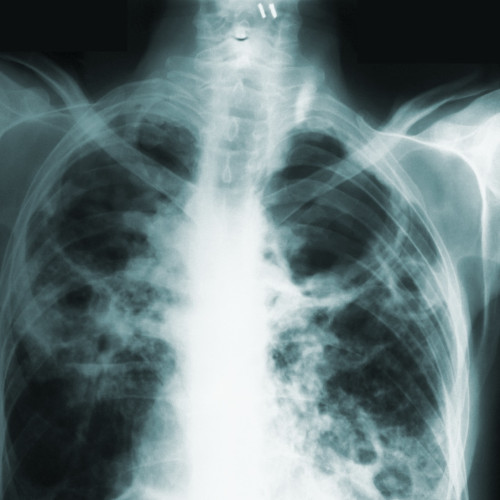

Rezident din Camden County în izolare după ce a fost testat pozitiv pentru tuberculoză

Autoritățile de sănătate din Camden County raportează că un rezident care a vizitat un spital local a fost testat pozitiv pentru tuberculoză activă. Rezidentul s-a prezentat la spital pe 12 februarie, având simptome conforme cu TB, conform unui comunicat de presă, potrivit nj.com.